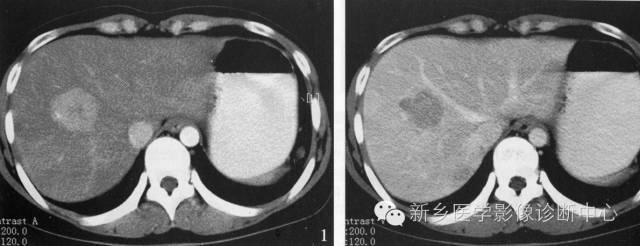

肝转移癌的CT表现因原发癌及病理组织类型不同而异。

平扫时:显示为多发性大小不等的低密度肿瘤结节,也可为单发结节。多在低密度内存在更低密度区域,从而显示为同心圆状或等高线状双重轮廓为其特征。

增强扫描:肿瘤境界清楚,边缘部分可增强而密度增高。1cm大小转移癌可出现类似环状增强的表现。

平滑肌肉瘤、软骨肉瘤、类癌、肾癌、胰岛素瘤、甲状腺癌等的肝转移癌血供丰富,动脉期及门脉期可见明显肿瘤增强征象。有时候与肝细胞癌难以鉴别,但其总体以环状增强为主要特征,再结合临床诊断很重要。